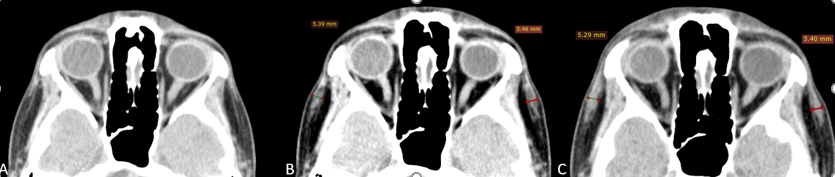

Данные МСКТ (рис. 3): на аксиальном срезе височной области в межфасциальном пространстве височной области имплантат определяется при исследовании сразу после инъецирования и через 21 день в виде включений толщиной 4–5 мм плотностью аналогичной мышечной ткани. В динамике через 21 день филлер приобретает более чёткие контуры и гомогенную структуру, а также определяется нивелирование посттравматических изменений.

Рис.3 МСКТ сканы височной области, аксиальная проекция.

А – до инъецирования

В – сразу после инъецирования, толщина имплантата слева 5,4 мм, справа 5,5 мм

С – через 3 недели, толщина имплантата слева 5,3 мм, справа 5,4 мм